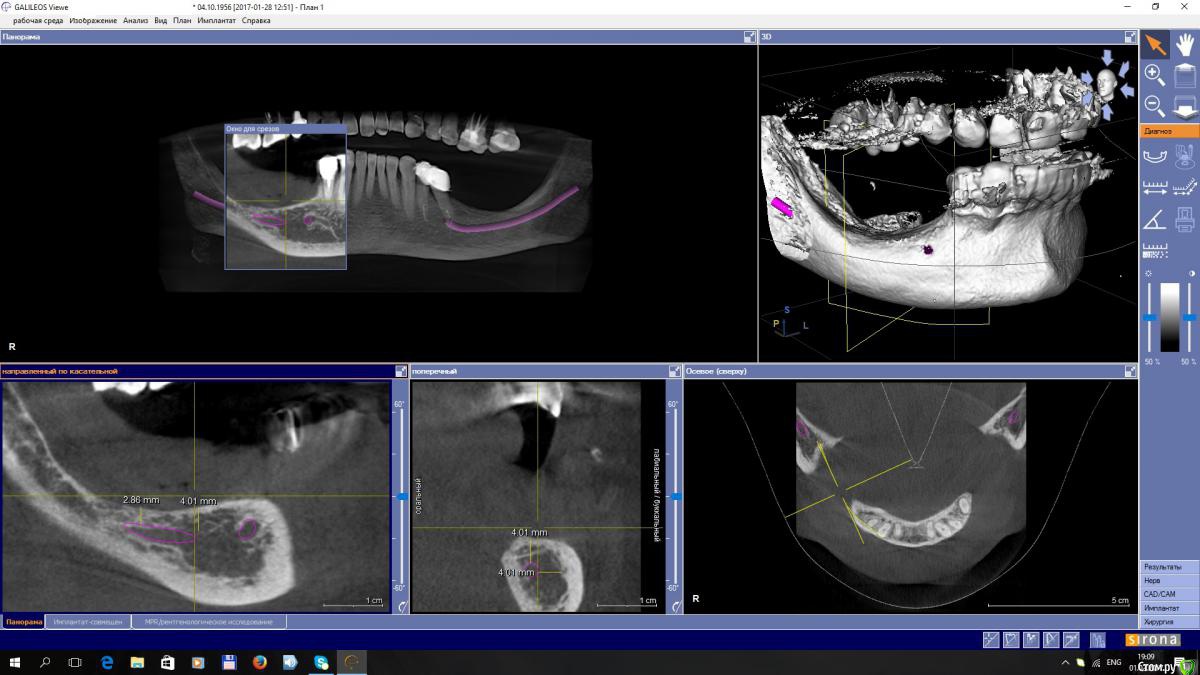

EEcho Опубликовано 3 февраля, 2017 Поделиться Опубликовано 3 февраля, 2017 Уважаемые коллеги! Я в раздумье.Максимально, кость я могу поднять на 4-5 мм, с одной и с другой стороны. Дальше не позволяет межальвеолярная высота.Делать репозицию нерва или все таки пластику с последующей постановкой коротких имплантов. Ссылка на комментарий